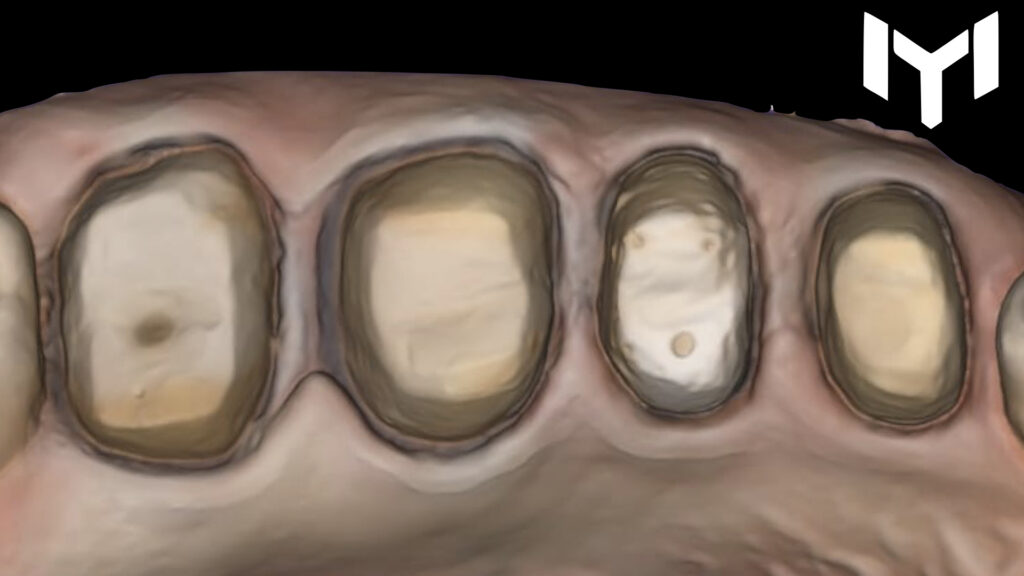

2. The Power of Temporization The “magic” happens during the healing phase. We placed high-quality provisional crowns for one month. This stage is crucial for:

• Guiding the gingival healing.

• Determining the ideal emergence profile.

• Ensuring the patient’s comfort and function before the final stage.